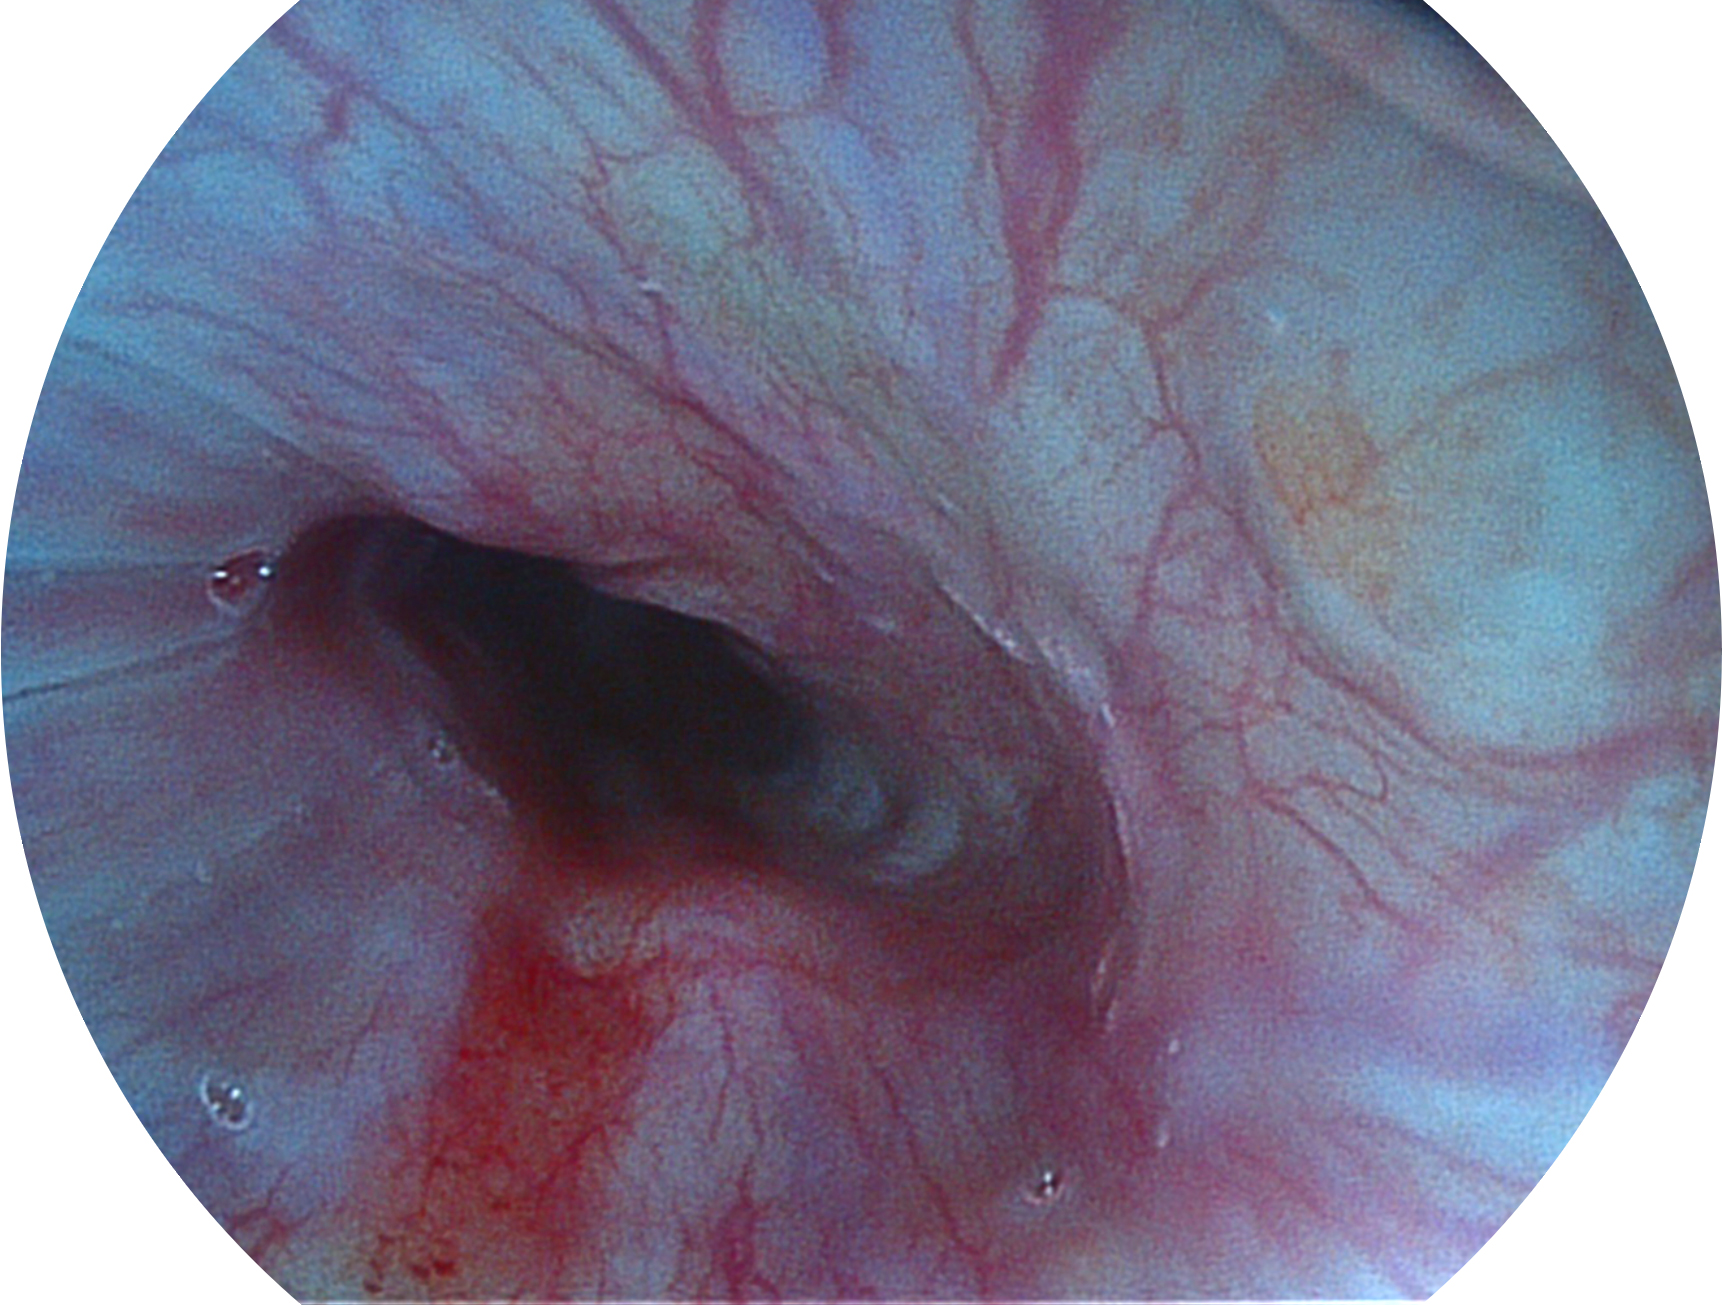

诸侯快讯官网新开发的内镜染色技术,主要是基于多波长LED 光源的开发,VLS-55Q 四波长LED 光源是由四个不同颜色的LED光按照相应照明模式所规定的特定发光比例进行合束后形成,合束后形成的照明光的光谱由红光、绿光、蓝光及蓝紫光这四个不同的波段范围构成。具有更高光谱自由度,通过光谱比例的控制,实现了聚谱成像技术,英文全称为“Spectral Focused Imaging, SFI”,缩写为“SFI”和光电复合染色成像技术,英文全称为“Versatile Intelligent Staining Technology, VIST”,缩写为“VIST”。